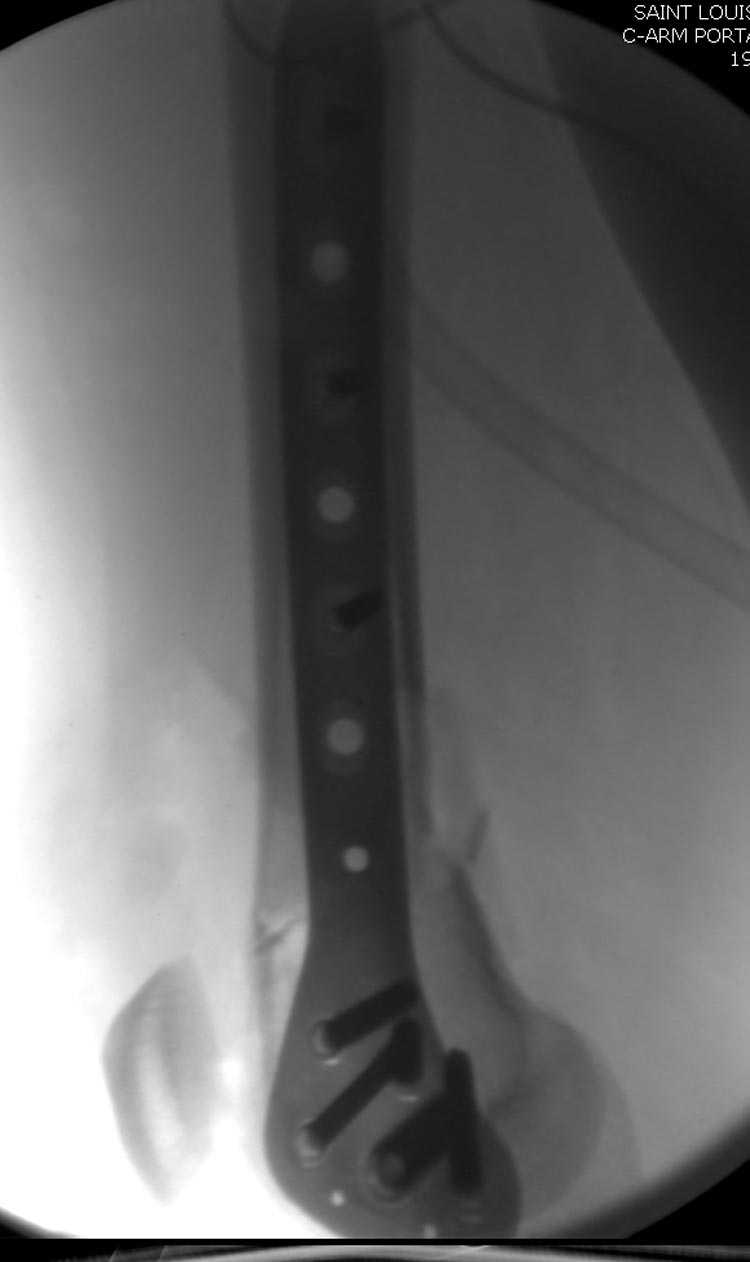

Смело открывайте сустав, собирайте мыщелки на один спонгиозник или болт стяжку и под него вводите штифт из стандарного места введения. В данном случае хорошо подойдет универсальный бедренный штифт СнМ.

Бесспорно, предлагаемый ретроградный метод имеет свои преимущества, но имеется опасность при манипуляции интрамедуллярным гвоздем расколоть мыщелки.

Раскол можно предупредить шурупами, но короткий дистальный фрагмент навряд ли позволит добиться адекватной стабильности конструкции. Стандартные гвозди не рассчитаны для таких переломов, и если все таки желаете провести фиксацию гвоздем, тогда надо заказывать специальный custom made nail т.е. с расширенной возможностью дистальной блокировки.